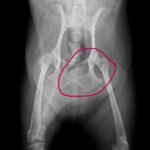

腫瘍は局所浸潤性が強く、肛門周囲組織や骨、筋肉に浸潤しやすいほか、リンパ節および肺への転移も高頻度で起こります。約50%の症例で転移が認められます。

血液検査では約25〜30%の症例で高カルシウム血症が認められます。その他、リンパ節腫大や遠隔転移の有無を評価するため、胸部および腹部のX線検査、超音波検査、CT検査が実施されます。